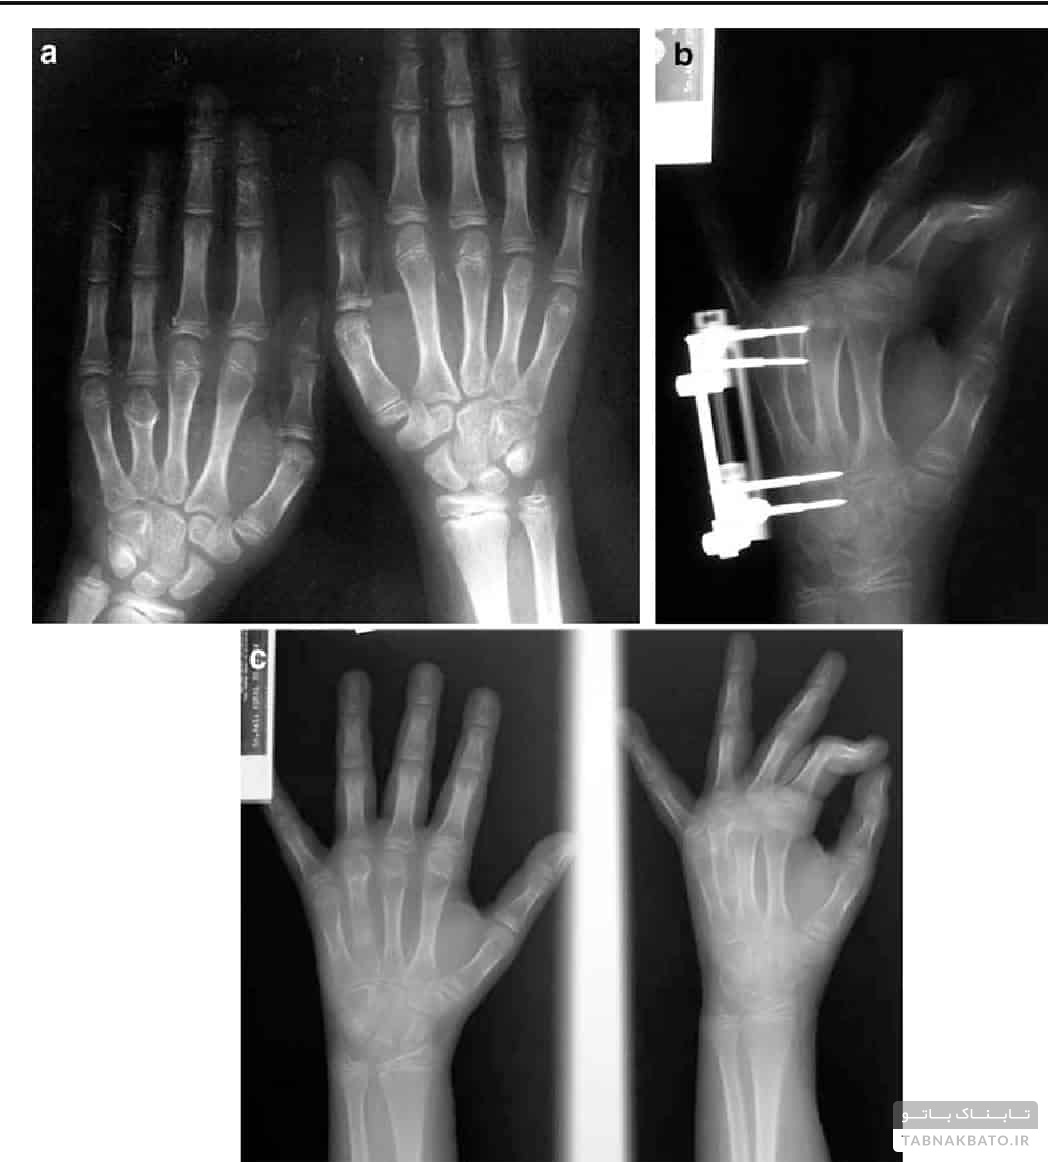

۳. استخوان‌سازی تحت کشش

یکی از روش‌های جدید برای درمان نقص رشد استخوان‌های بدن استخوان سازی تحت کشش" است. پایه فکری این تئوری خیلی جدید نیست.استفاده از این روش به زمان بقراط بر می‌گردد که از یک نیروی خارجی در استخوان شکسته یک پای کوتاه جهت رفع این نقیصه استفاده می‌شد. یک جراح روسی بنام گابریل الیزاروف در سال ۱۹۵۰ این تئوری را گسترش داد. با این روش به محل جدایی دو قطعه استخوان به تدریج نیرو وارد می‌شود و باعث استخوانسازی در این فضا می‌گردد که این تدریجی بودن نیروها باعث تطابق تدریجی بافت‌های نرم شامل ماهیچه ها - تاندون ها - اعصاب و عروق نیز خواهد شد.